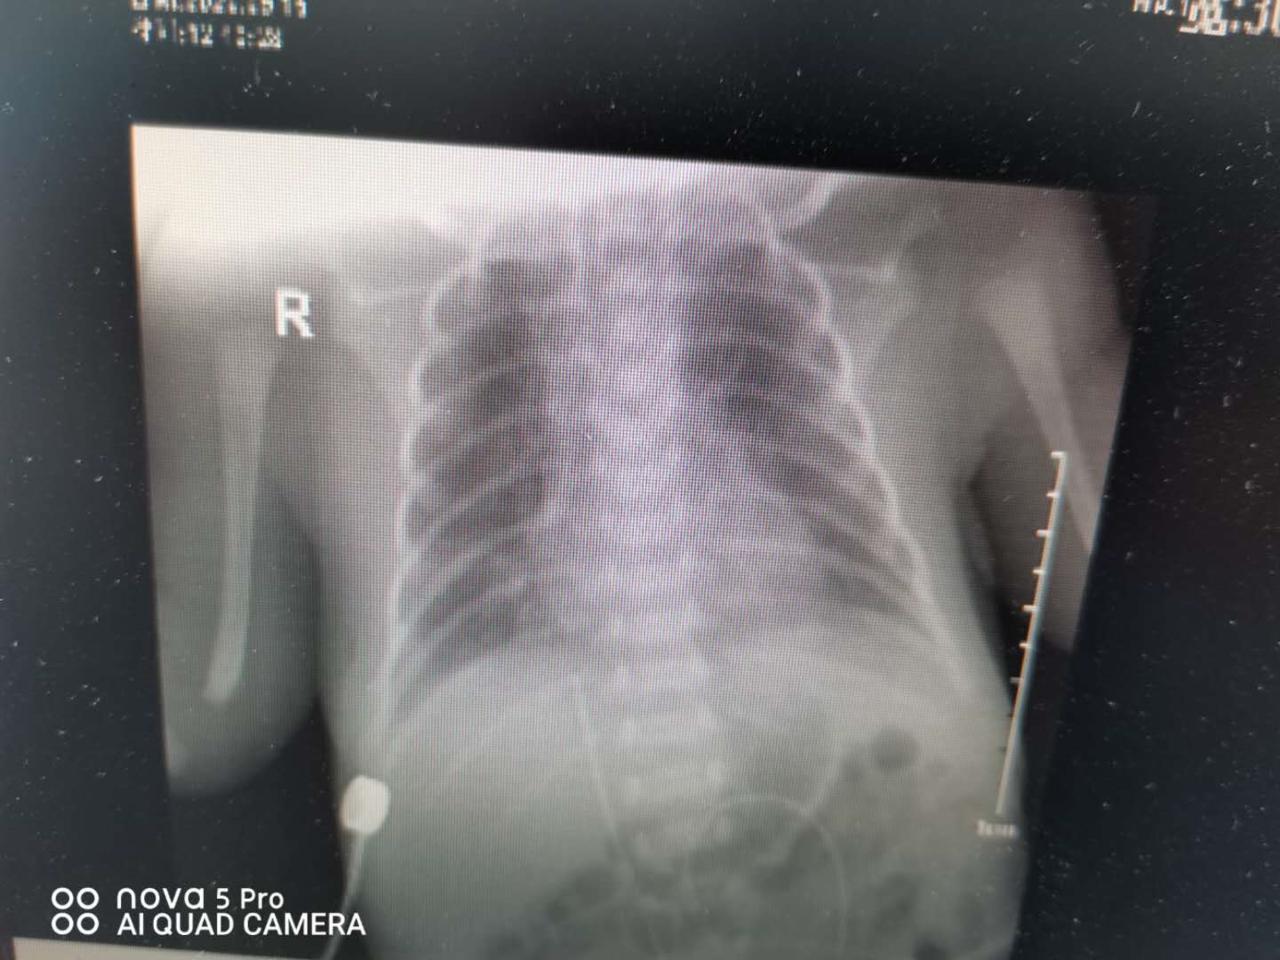

前天,我院儿科一病区收治一名30周,体重1600g的早产儿,出生后呼吸费力,经过诊断,确诊为新生儿呼吸窘迫综合征。随后经过商议给予肺表面活性物质、常频机械通气等治疗,患儿症状一度好转。就在今晨,患儿出现经皮氧饱和度下降,肢体青紫,100%吸入氧浓度常频机械通气不能维持,急行床旁胸片示左侧气胸,考虑肺发育不良并发自发气胸,予以胸腔穿刺闭式引流术,高频呼吸机通气后,症状好转。

(常频通气后)

高频呼吸机是我院今年为我科新购置的高端设备,在治疗新生儿持续肺动脉高压方面优势明显。我们采用高频通气,使用后患儿经皮氧饱和度很快升至93%左右。